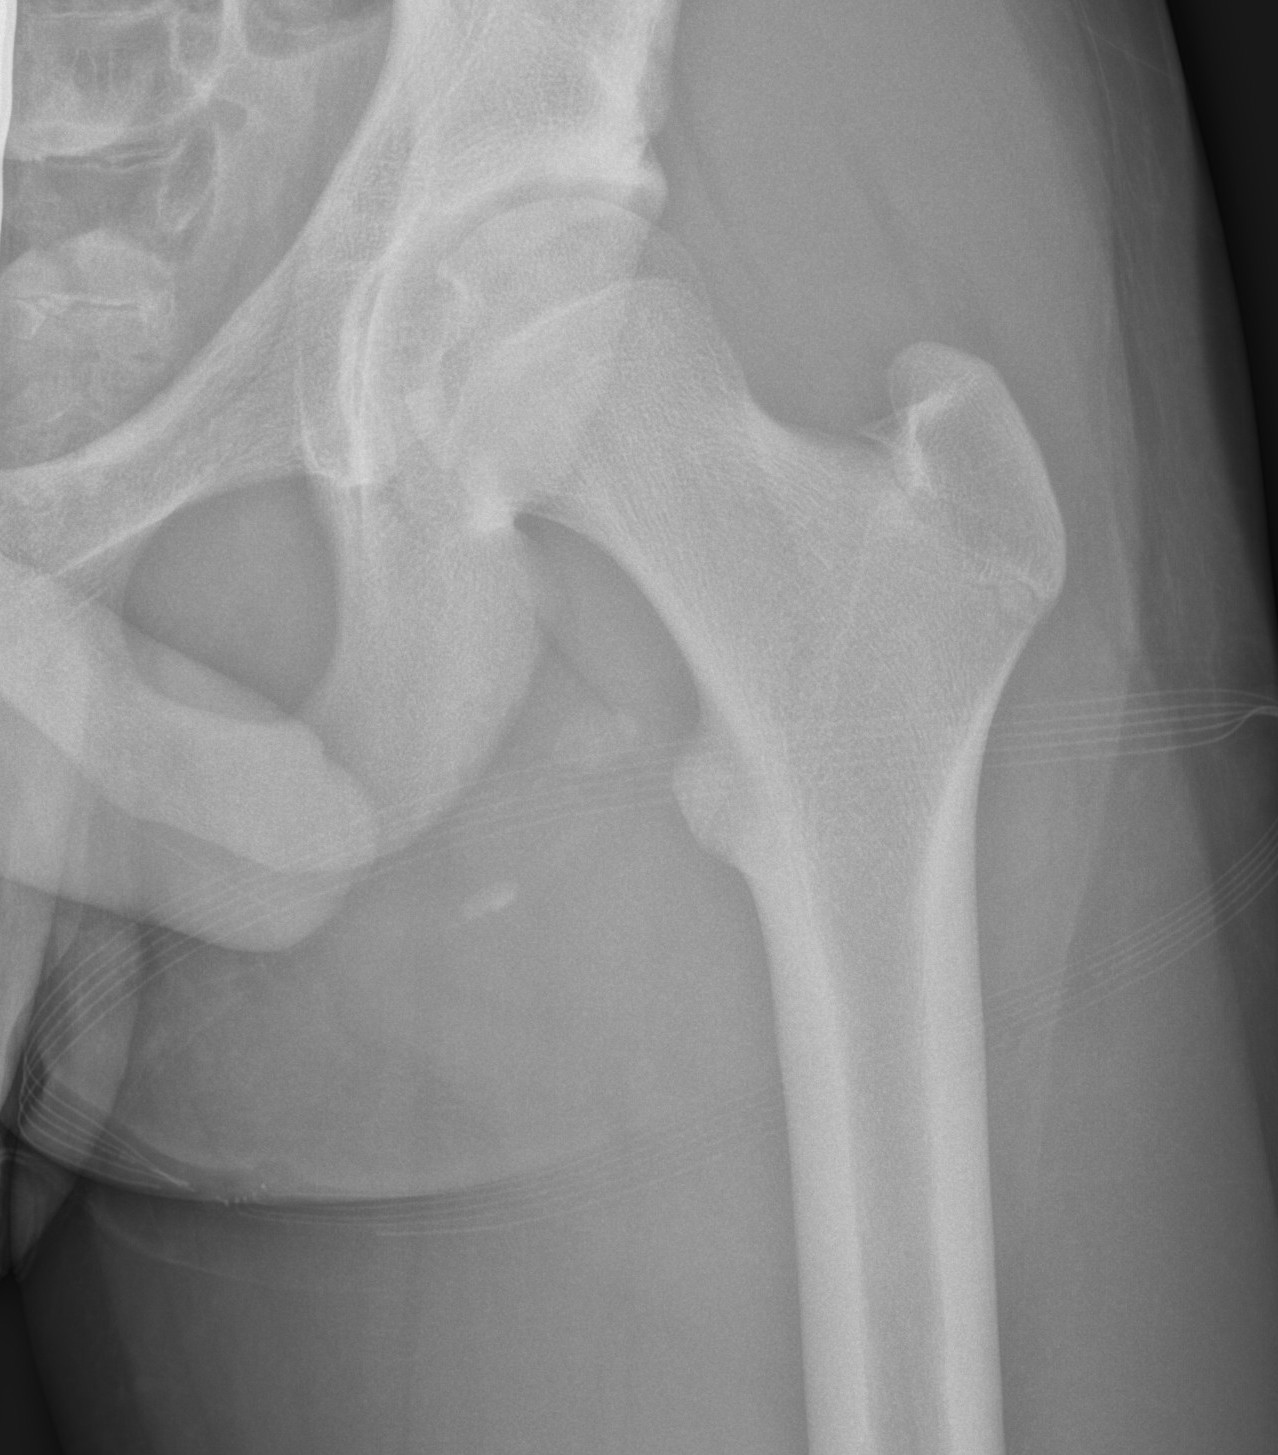

Xray

Ischial tuberosity avulsion 1Ischial tuberosity avulsion 2

Ischial tuberosity avulsion